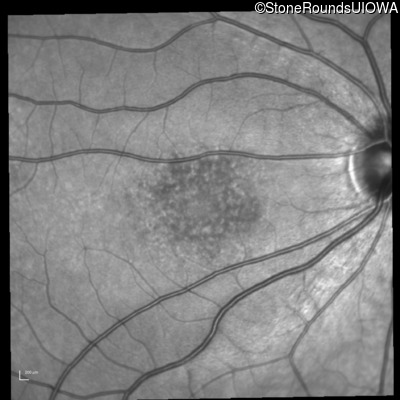

Infrared Fundus Photograph - Left - 20/50

Exemplar